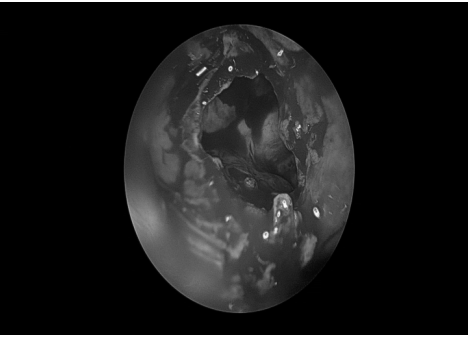

耳内镜检查:分泌性中耳炎(右)

双耳鼓膜完整,右侧鼓膜内陷明显,右侧鼓室可见积液